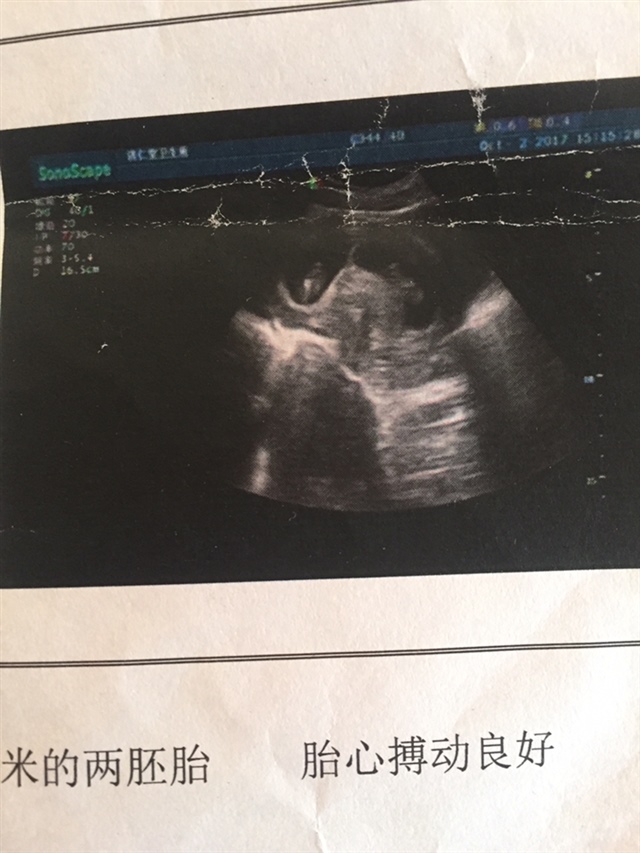

看着像异卵,像龙凤胎

你看你的B超结果,是一个孕囊还是两个?但是看着你发出的情况,应该是单卵,看着中间好像有分隔。

好像龙凤双胞胎

上面我写了啊!两胚胎。你这个是双胎。恭喜🎊